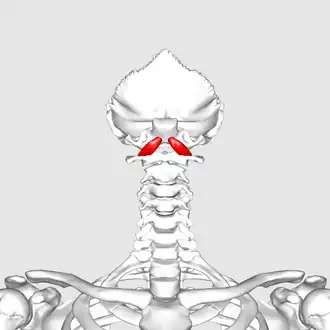

Anterior view of rectus capitis anterior muscle. Skull has been removed (except for occipital bone) | |

Animation. Position of rectus capitis anterior muscle. Some bones around the muscle are shown in semi-transparent.

Animation. Position of rectus capitis anterior muscle. Some bones around the muscle are shown in semi-transparent. -

Skull has been removed (except for occipital bone)

Skull has been removed (except for occipital bone) -